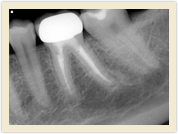

![]() |

| Before Photo | After Photo |